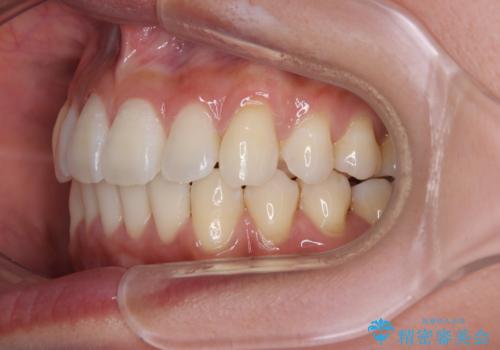

前に飛び出した上顎前歯をスッキリと引っ込める ワイヤー装置での矯正治療

- 上顎前歯の突出感を気にして来院された患者様です。

舌の突出癖の影響で、歯列が前方に飛び出いた形態となっている状態でした。

抜歯矯正とするような歯列ではないため、舌のトレーニングを行いながら歯列を側方に拡大させることで口元の突出感を改善することとしました。

横顔は元々突出した印象ではなかったのですが、上顎前歯の角度が改善したことで、唇の閉じにくさが改善されました。